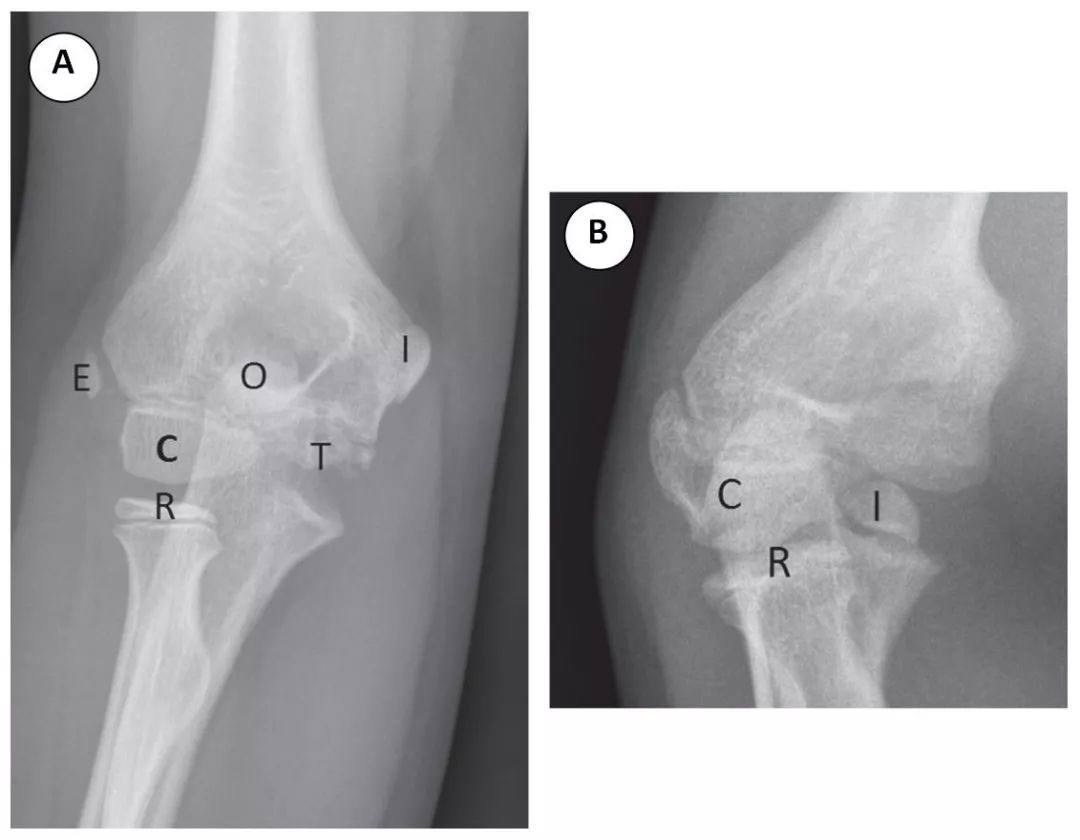

肘部出现非骨化或未完全骨化的次级骨化中心是儿童所特有的。熟悉肘部骨化中心的外观和出现顺序是识别正常解剖和避免骨折误诊的关键。肘部有 6 个次级骨化中心,它们的出现和骨化的顺序取决于儿童的年龄和性别。CRITOE 是对骨化中心出现序列的一种助记符。CRITOE 分别代表小头肱骨小头、桡骨头、内上髁、滑车、鹰嘴及外上髁骨化中心 (图 2A)。了解骨化中心序列的一个重要方面是滑车骨骨化中心出现在内侧上髁骨化之后。当内侧上髁骨折移位进入滑车区域时,不要误认为这是正常的肘关节发育。注意,滑车骨骨化中心不应出现在内上髁骨化中心之前 (图 2B)。如果没有认识到正常的骨化中心出现的顺序,移位的内上髁骨折可能被漏诊。

图 2 (A) CRITOE 是关于骨化中心外观可预测顺序的助记符。CRITOE 代表肘关节正位片上可见的肱骨小头 (C)、桡骨头 (R)、内上髁 (I)、滑车 (T)、鹰嘴 (O) 和外上髁 (E) 骨化中心。(B) 在肱骨滑车沟中注意移位的内上髁,不要将其误认为是肘关节前部可见的正常滑车骨化中心。